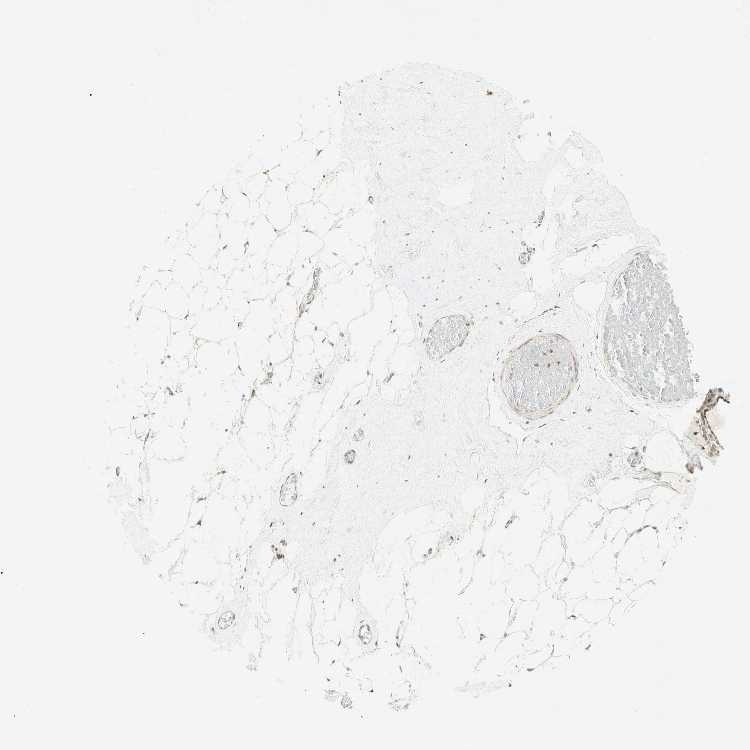

BREAST - Antibody stainingi

Antibody staining in the annotated cell types in the current human tissue is reported as not detected, low, medium, or high, based on conventional immunohistochemistry profiling in selected tissues. This score is based on the combination of the staining intensity and fraction of stained cells.

Each image is clickable and will lead to virtual microscopy that enables deeper exploration of all samples and also displays staining intensity scores, fraction scores and subcellular localization as well as patient and tissue information for each sample.

Antibody HPA039853Antibody CAB010206

Adipocytes Not detectedLow

Glandular cells Not detectedLow

Myoepithelial cells MediumLow